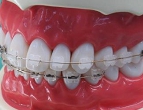

低摩擦クリア矯正装置

設定した治療ゴールにすばやく到達するためには,歯を低摩擦(ローフリクション)で移動させることが重要です.当院では「ローフリクションtypeのブラケットシステム」を採用しています.

当院のワイヤー矯正は,歯の移動抵抗が少なく

歯周組織への負担が少ないライトフォースな

矯正ワイヤーと審美クリアブラケットを使用して,

矯正中の快適さに配慮した治療を行っています.